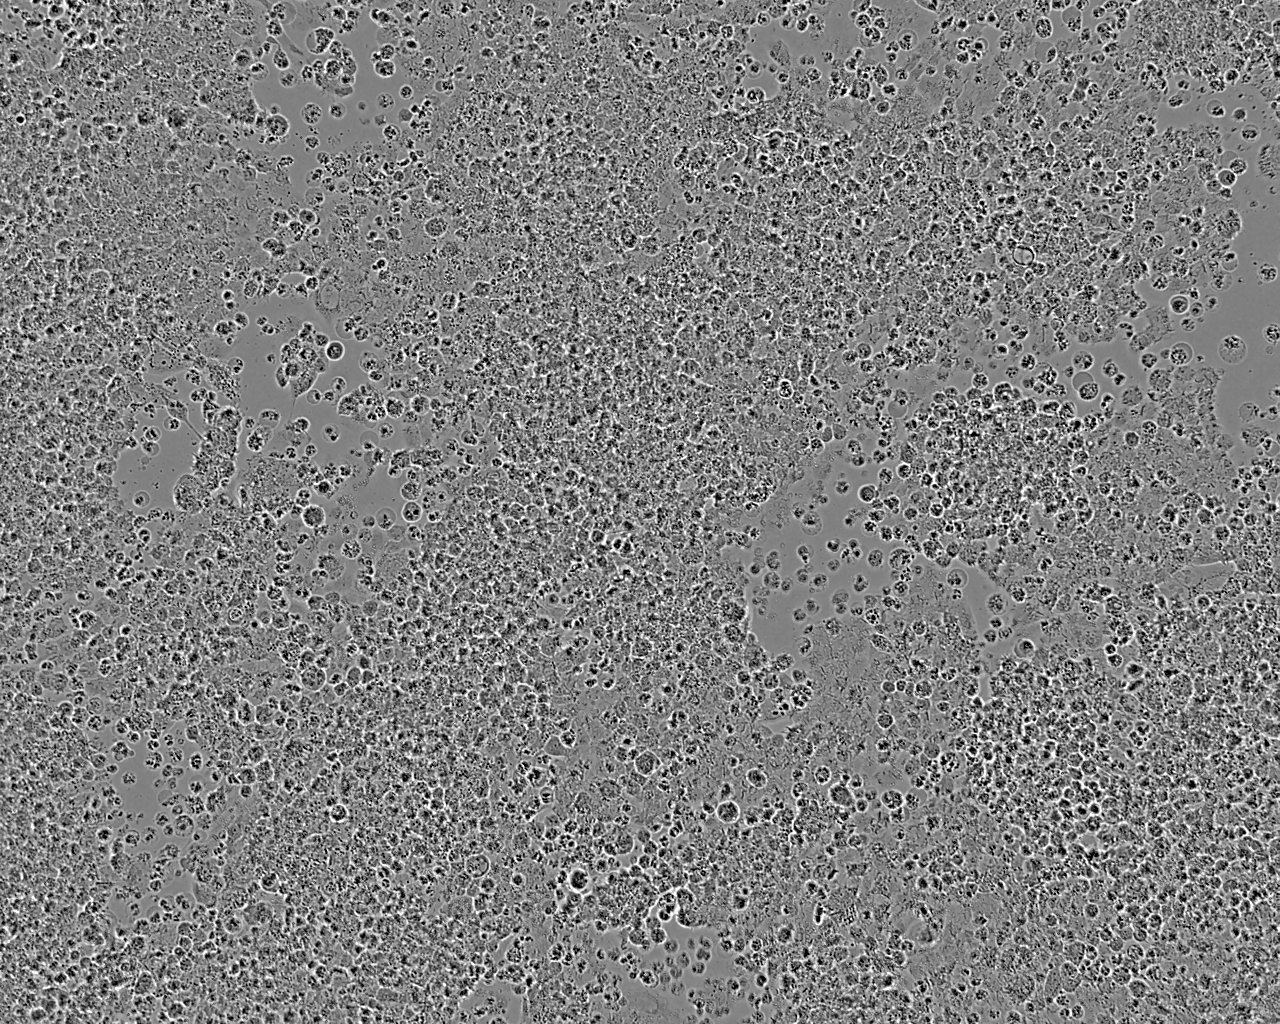

多边形和纺锤形

| 细胞详情 |

COV434卵巢颗粒肿瘤细胞 |

卵巢 |

| 细胞形态 |

多边形和纺锤形 |

| 生长方式 |

贴壁生长 |

| 描 述 |

从实体原发肿瘤建立的卵巢颗粒瘤细胞系。 |

| 培养条件 |

DMEM,10%胎牛血清;空气95%,二氧化碳5%;37℃培养 |

ECACC参考图片: